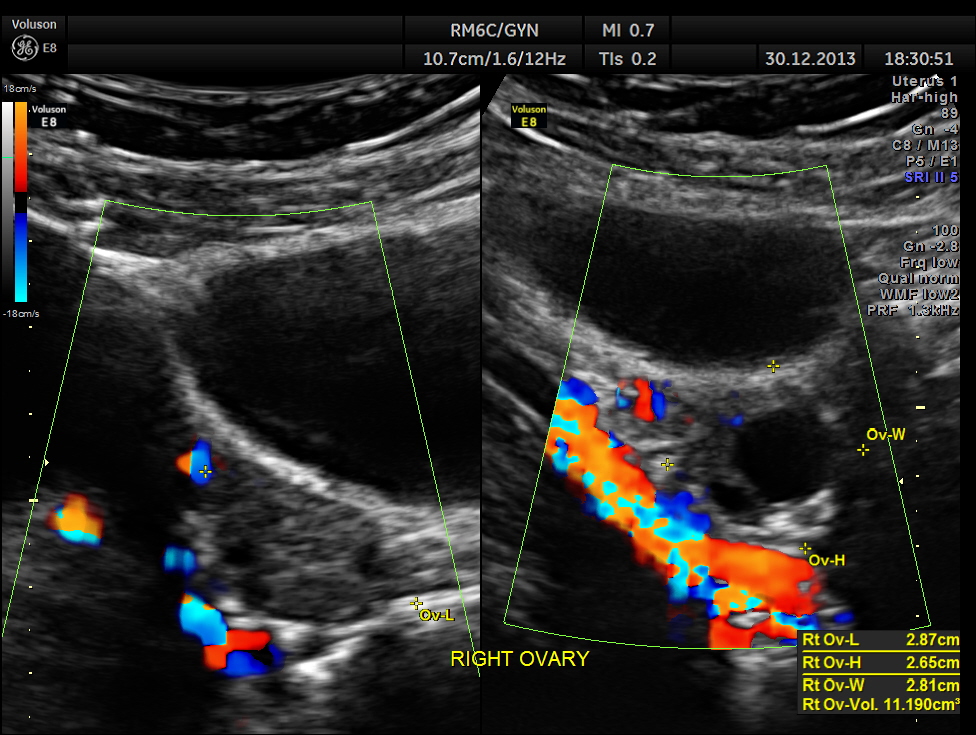

the ovaries are shown below.